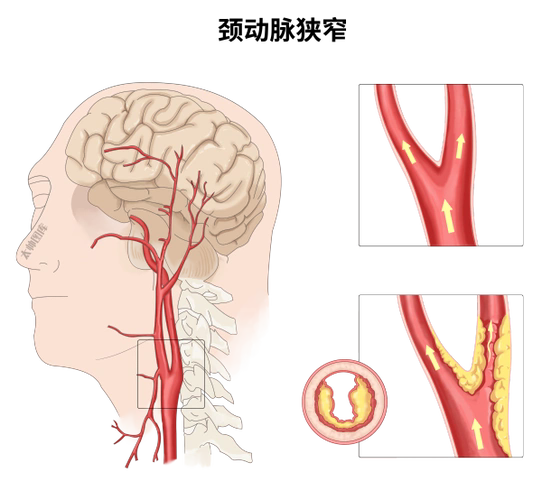

随着人们生活水平提高和人口老龄化,缺血性脑卒中(即脑梗)的发病率越来越高,颈动脉狭窄是缺血性脑卒中发生的主要原因之一。张爷爷此次病发,便是颈动脉狭窄惹的祸。

神经外科主任曾怀文介绍, 由于年龄增加,血管老化、血脂沉积,会逐渐形成动脉粥样硬化,再加上高血压、高血糖、吸烟、酗酒等不良因素,都会加重动脉粥样硬化斑块。

久而久之,血液脂质、杂质沉积附着于颈动脉血管壁,斑块逐渐增大阻塞血管腔造成管腔的狭窄,严重时甚至造成管腔的闭塞,导致相应区域的供血不足,这就是颈动脉狭窄。

颈动脉狭窄症本身没有典型的临床表现,常不易发现。在早期的临床表现有突然发作的麻木、感觉减退或感觉异常、上肢或下肢无力、面肌麻痹和单眼突然发黑等,如发生在大脑优势半球,可引起语言障碍。这种症状的出现有时仅数分钟,也可数小时,但在24小时内完全消失,上述症状临床上称为短暂性脑缺血发作(TIA),也就是俗称的 “小中风”。严重者便会出现脑梗塞的症状,可引起死亡或遗留严重后遗症。